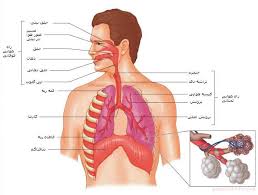

قیمت: 88٬000 تومان - دسته بندی فایل: پاورپوینتپاورپوینت نارسایی حاد تنفسی

فروش ویژه پاورپوینت حرفه ای نارسایی حاد تنفسی با تخفیف استثنایی فقط 69 هزار تومان تعداد اسلاید : 57 اسلاید